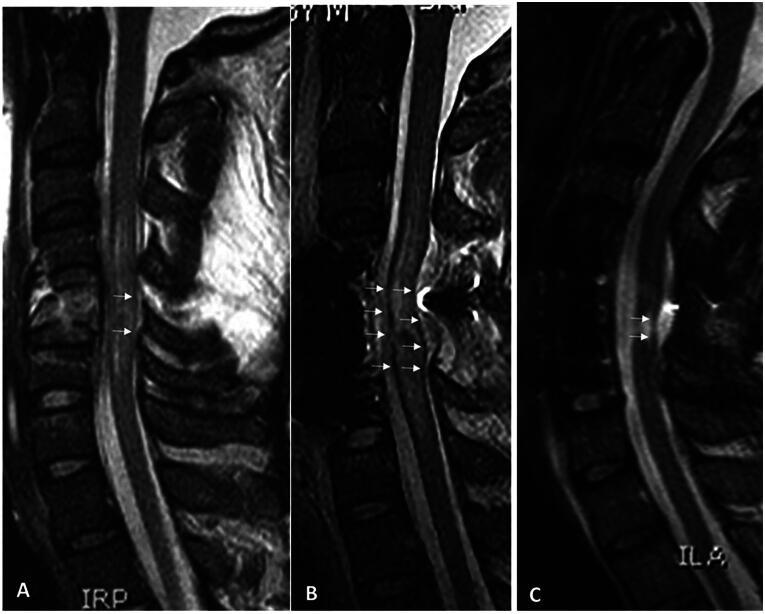

Spinal cord injury (SCI) remains a major unsolved problem that permanently impairs the lives of innumerable individuals worldwide. Although advances in the basic, pre-clinical and clinical sciences of SCI hold promise for patients, clinicians may lack a full insight into the relevant cellular and molecular events, and laboratory researchers may underappreciate how cellular and molecular phenomena translate into meaningful functional outcomes. To help bridge these perspectives, we first review the American Spinal Injury Association (ASIA) Impairment Scale (AIS) grade, which is the principal instrument used to gauge clinical outcomes in SCI, and the clinically important concept of AIS grade "conversion" (improvement), which occurs in some but not all patients. We then review underlying mechanisms that contribute to the AIS grade and its conversion, including mechanisms of transient neurological dysfunction (neuronal and axonal "stunning"), mechanisms of secondary cell loss (apoptosis, pyroptosis, and necroptosis), and mechanisms of axonal loss (primary axotomy and secondary axonal degeneration). Finally, we briefly review approaches to clinical management that may ameliorate identified mechanisms of secondary tissue loss and neurological dysfunction following SCI.